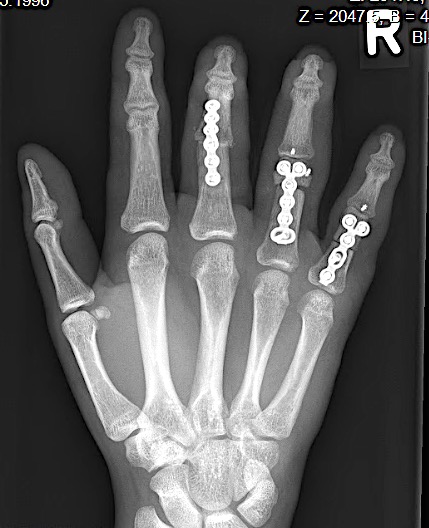

A 20-year-old male suffered a complex multi-digit injury of the right hand requiring revascularization and stabilization of both proximal phalanx and PIP joint fractures (Figs 5 - 8). Multiple plates, including the rotation correction plate from the 1.5 module of the VA Locking Hand System were used for fixation. The Variable Angle Locking system is ideal when only two screws, either proximal or distal, are able to be inserted due to space limitation.

One major advantage of variable angle technology in very distal phalangeal fractures is the ability to be extremely flexible with a wide range of fixation options. Freedom of implant placement assists early mobilization, vital in these complex fractures with associated soft-tissue trauma.